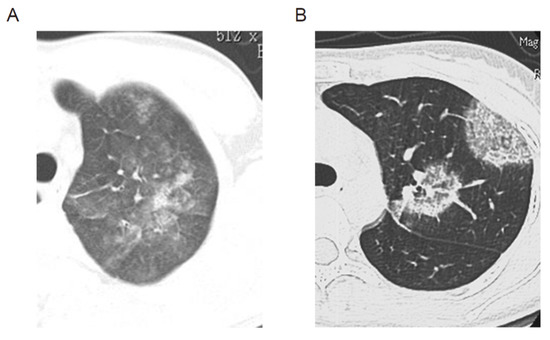

2. AEP and CEP